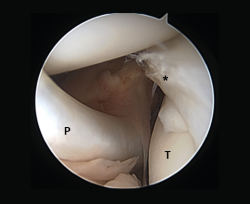

Other diagnostic tests are radiographs under stress varus conditions. We can find indirect radiological signs such as Segond fracture and the arcuate sign. MRI is of great help. Gelber et al. recently reported that over 80% of a group of world experts in the treatment of posterolateral angle injuries agree on the usefulness of MRI in the diagnosis of these lesions(17). Lastly, arthroscopy can offer additional information in the surgical cases (Figure 2).

Figure 2. Arthroscopic view through the anterolateral port of damage to the meniscus-popliteal ligaments (*) at the level of the popliteal hiatus, leaving the tibia exposed (T). P: tendon of the popliteus muscle. Right knee.